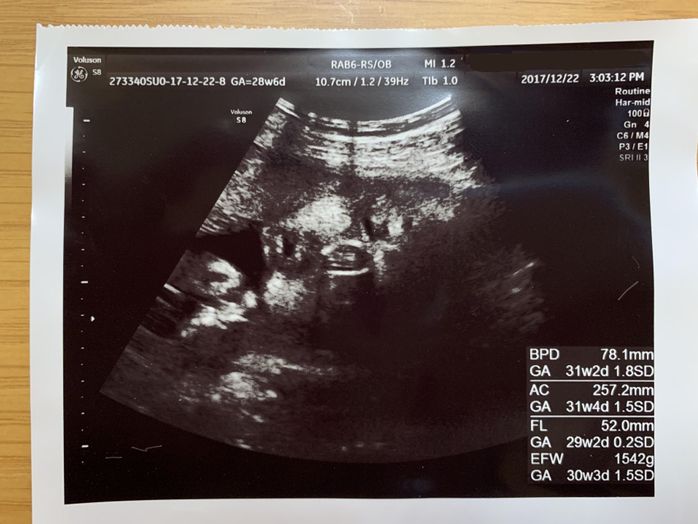

妊娠28週目 免疫力低下? マイコプラズマ肺炎に…

妊娠28週目。ちょうど妊娠8ヶ月に入ったところで、私はマイコプラズマ肺炎にかかってしまいました。上の子どもたちの相手をすることもできず、おなかの赤ちゃんへの影響も心配。病院の先生からは、赤ちゃんに影響のない抗生剤を処方していただきましたが、仕事もしばらくお休みしなければなりませんでした。その頃は、昼夜を問わず動き回る、元気のいい胎動だけが心の支えでした。